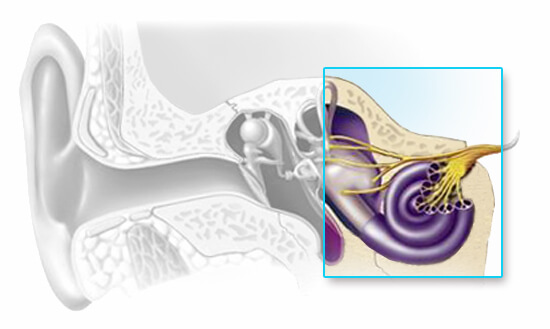

Sensorineural Hearing Loss

Sensorineural hearing loss results from inner ear or auditory nerve dysfunction. The sensory component may be from damage to the organ of Corti, an inability of the hair cells to stimulate the nerves of hearing or a metabolic problem in the fluids of the inner ear. The neural or retrocochlear component can be the result of severe damage to the organ of Corti that causes the nerves of hearing to degenerate or it can be an inability of the hearing nerves themselves to convey neuro chemical information through the central auditory pathways.

The reason for sensorineural hearing loss sometimes cannot be determined, it does not typically respond favorably to medical treatment, and it is typically described as an irreversible, permanent condition. Like conductive hearing loss, sensorineural hearing loss reduces the intensity of sound, but it might also introduce an element of distortion into what is heard resulting in sounds being unclear even when they are loud enough. Once any medically treatable conditions have been ruled out, individuals with a sensorineural hearing loss can be fit with hearing aids to give them access to speech and other important sounds.